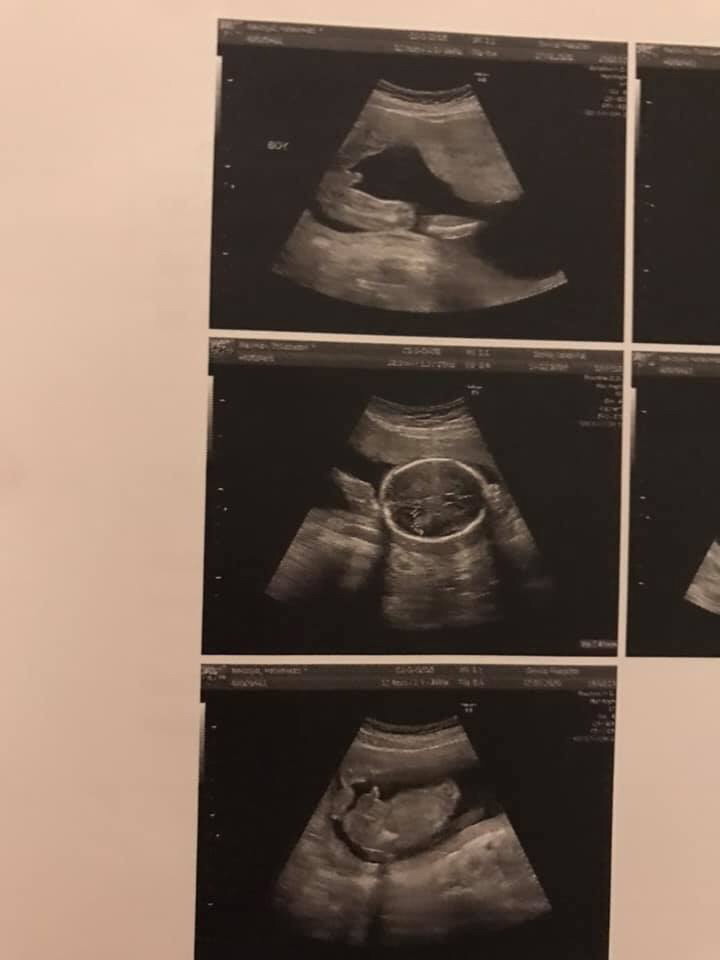

ชายจ้า 4 กค

ผช.แน่เลย